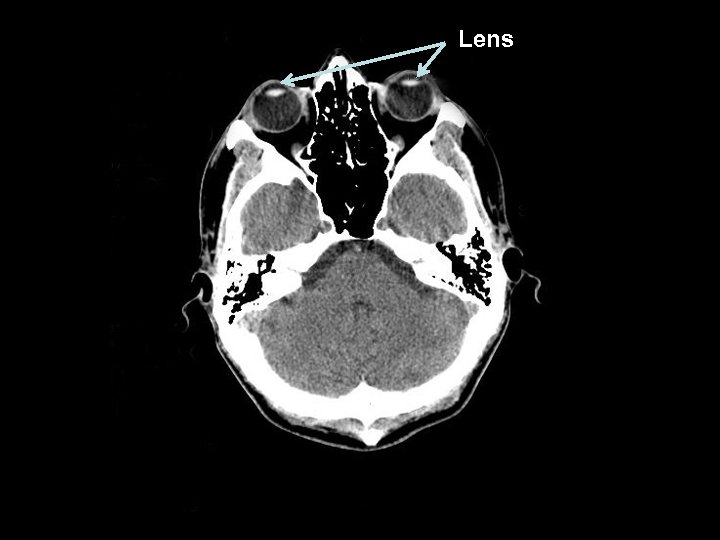

Lens

Initial Audit Method § A retrospective sample of 50 consecutive CT head scans were chosen at both trust sites. § The patient demographics, examination indication and the exposure of both, one or neither lens were collected from review of the PACS and CRIS systems. § Those patients scanned whilst in a neck collar were excluded from the audit.

Problem Analysis § The most significant reason for the inclusion of lenses on § CT head examinations is incorrect patient positioning. The patient should be positioned with the neck flexed and CT gantry tilted.

Problem Analysis § The most significant reason for the inclusion of lenses on § CT head examinations is incorrect patient positioning. The patient should be positioned with the neck flexed and CT gantry tilted. § Responsible factors: § Patient immobilisation (these patients were excluded) § Patient inability (with increasing age some patients are unable to comply, this may explain the age differential) § Inadequate equipment § Inadequate planning